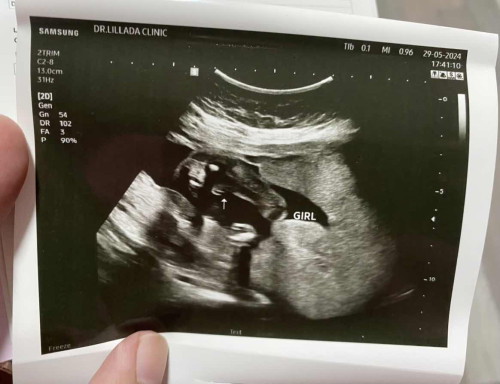

20 สัปดาห์ 4 วัน

แม่ๆคะ แบบนี้น้อง ผญ 100% ไหมค่ะ